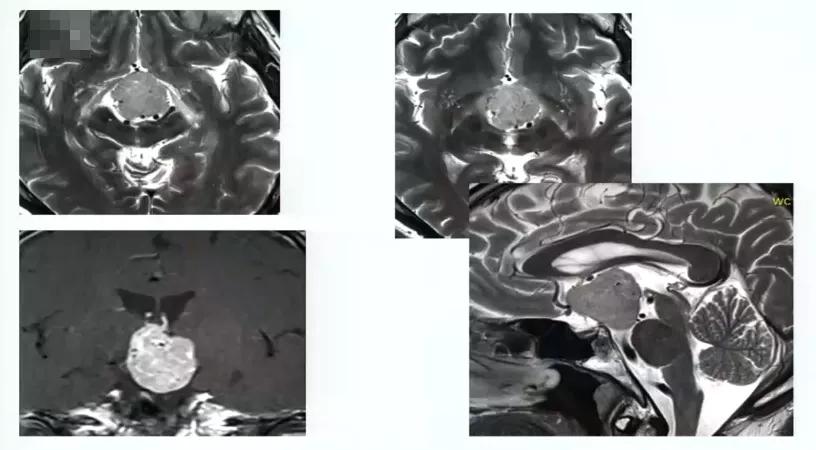

视路胶质瘤全切手术病例4:

50岁男性,出现严重视野缺损

图:术前MRI

图:术中核磁辅助手术后,进行术中检查看是否在角落里有残留肿瘤。 术中检查及术后核磁均显示肿瘤完全切除。